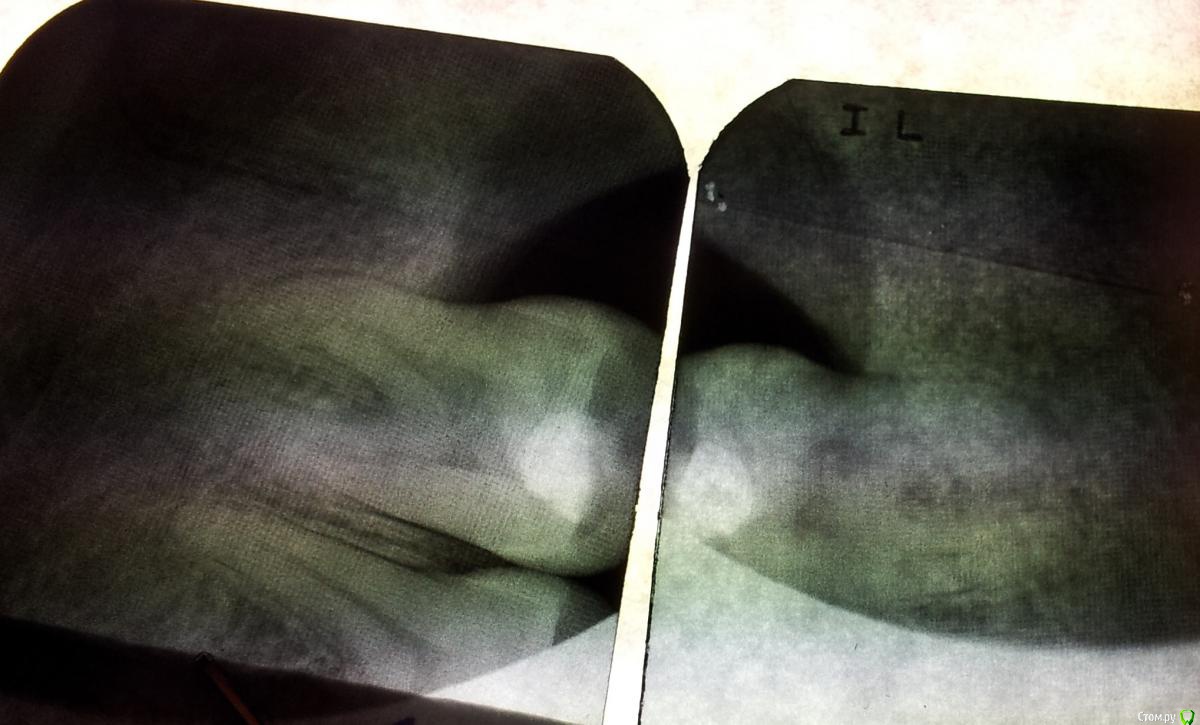

k_d_a Опубликовано 6 ноября, 2015 Автор Поделиться Опубликовано 6 ноября, 2015 Вот снимки. Качество некоторых не очень получилось так что простите. Если будут считать что я очень плохой фотограф то вечером отсканирую ))) Самый первый снимок начал желтеть так что вот.... Ну и из-за того что я снимки фоткал на камеру телефона то одни и те же снимки будут несколько раз чтобы каждый сам выбрал какой лучше. Ссылка на комментарий